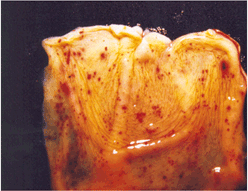

주요임상증상